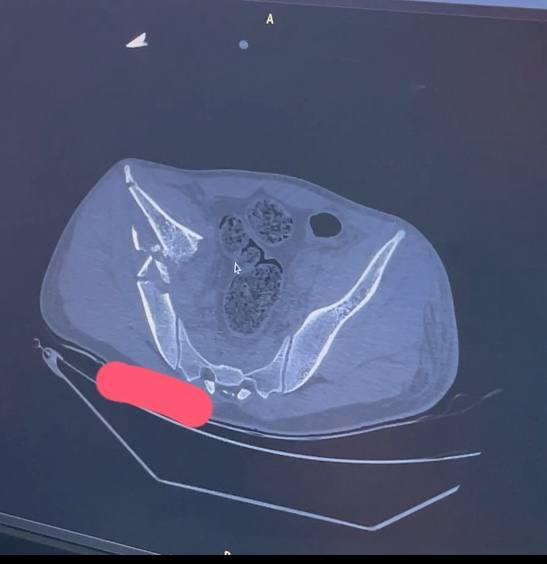

Спасли после падения с четвёртого этажа пациента травматологи больницы скорой помощи им. Подгорбунского

Тазовые кости мужчины практически полностью раздробились. Левое бедро закрепили штифтом, правую часть таза собрали по кусочкам за три операции. Сейчас мужчина идёт на поправку.